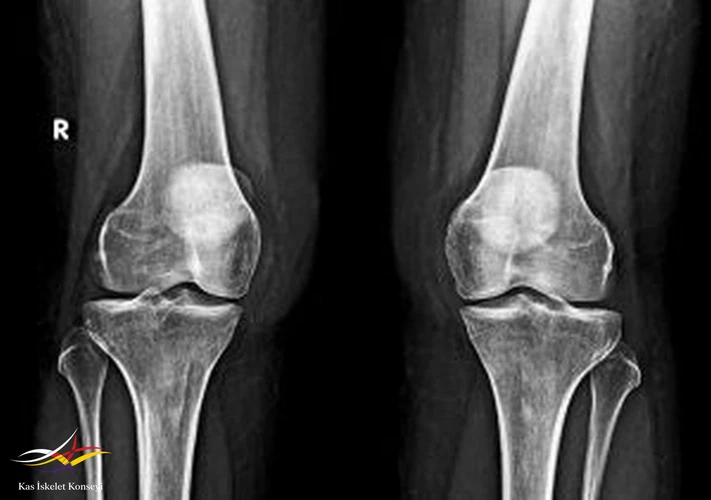

OLGU 220504Diz Ağrısı, Dizde Şişlik, Genu Valgus

Şikayet: Dizlerde şişlik ve sağda daha çok olmak üzere ağrı.

İncelemeler: MRG: Sağ dizde valgus deformitesi, bursit, cilt altı ödemle uyumlu. AFR'ler normal düzeyde.

Resim 1. Direkt diz grafisi.

Valgus deformitesi için hipermobilite ve pes planus sorgulanacak. Cilt altı ödem KBY'e sekonder? Ağrıda artış olması durumunda steroid enjeksiyonu düşünülebilir.